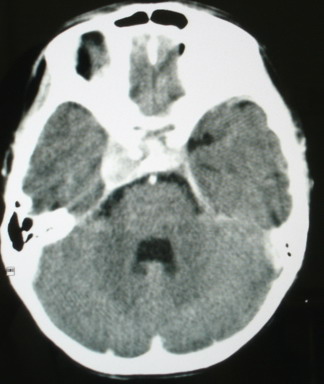

m/8y/,右侧眼睑下垂数日,发育良好,无外伤史,无头痛、恶心、呕吐,学习成绩良好。

ct意见:1、颅内血管畸形。2、右侧海绵窦血管瘤(颈内动脉海绵窦段动脉瘤)。3、脑萎缩。4、建议mr或dsa.

增强片

右侧海绵窦血管瘤伴右侧海绵窦漏形成(由于右眼上静脉较左侧增粗。故考虑)。

支持 右侧颈内动脉海绵窦瘘.注意眶内静脉有扩张.